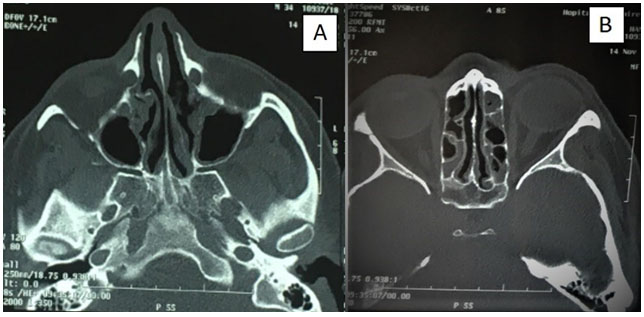

Complete blood count (CBC) showed hypereosinophilia to 7200 cells/mm3 with elevated erythrocyte sedimentation rate to 49 mm/h. Spirometry revealed obstructive syndrome. Electrocardiogram and transthoracic echocardiography were normal. Chest and paranasal sinus CT demonstrated ground-glass opacities (Figure 1) and severe pansinusitis (Figure 2). Skin biopsy showed necrotizing vasculitis with eosinophils (Figure 3) and ANCA were negative.

Figure 2: Paranasal sinus computed tomography (CT) demonstrated maxillary sinusitis (A) with severe ethmoidal sinusitis (B).